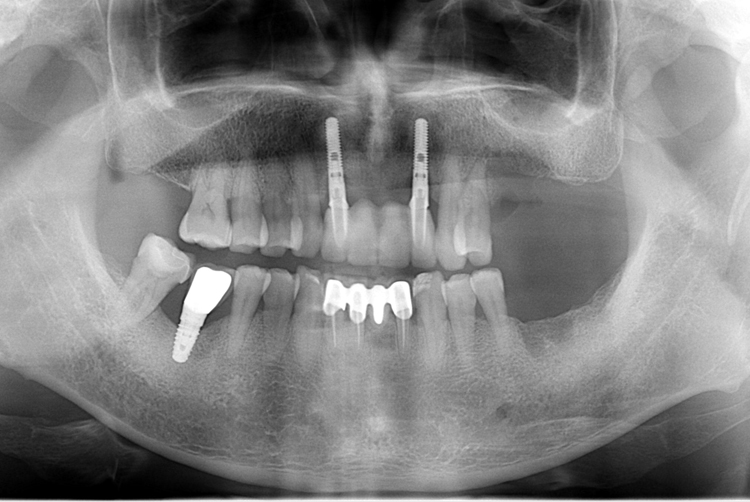

[임플란트] 앞니 임플란트

치료전 : 2018-07-11

치료후 : 2018-09-21

세종치과는 많은 환자와 다양한 케이스를 바탕으로

항상 편안한 임플란트 수술을 제공하고자 노력하고,

오래동안 튼튼히 쓸 수 있는 임플란트 수술을 가장 큰 목표로 삼고 있습니다.